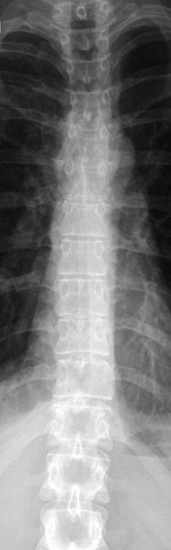

Рентгенография грудного отдела позвоночника – важный метод скринингового исследования, который позволяет оценить состояние грудного отдела позвоночника. Диагностическая услуга выполняется в двух проекциях.

Показания для проведения рентгена грудного отдела позвоночника:

• боли и дискомфорт в грудном отделе позвоночника;

• слабость в ногах;

• ограничение подвижности в грудном отделе позвоночника.